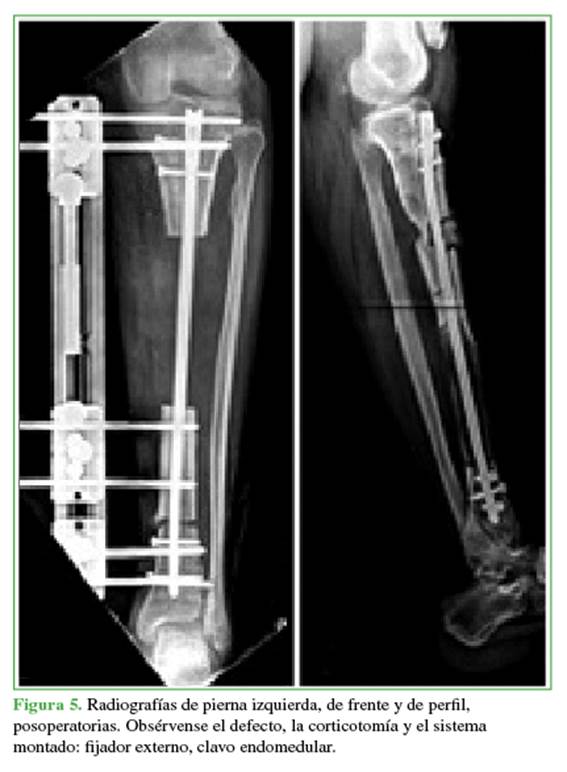

La segunda etapa es la reconstrucción ósea (dentro de las 6-8 semanas de la primera etapa) según la técnica original de Masquelet.11 El primer gesto consiste en la retirada del espaciador de cemento implantado mediante el mismo abordaje utilizado en la primera cirugía, o el levantamiento del colgajo de cobertura. Siempre se respetó la membrana periespaciador a fin de preservar su capacidad osteogénica. Se procedió al cambio de la osteosíntesis por un clavo sin cobertura de cemento de pequeño diámetro (8-9 mm) y a un nuevo fresado del canal para tomar nuevas muestras. Se colocaron los clavos de Schanz del fijador externo; en ocho pacientes (80%), se utilizó un tutor monolateral y, en el resto (20%), un tutor circular. Se efectuó una corticotomía metafisaria en el segmento remanente más largo.

El último paso consistió en la colocación del sistema de distracción y se comprobó la correcta distracción de la corticotomía (Figuras 4 y 5).